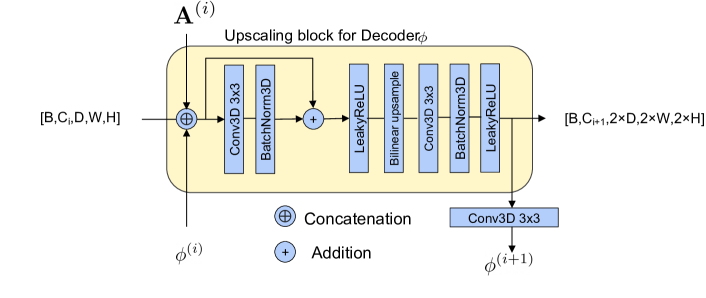

We then apply these transforms in a cascaded, multiscale fashion at increasing scales. For generation, the decoder is split into two backbones – Decoderϕ and DecoderA (Fig. 1). Each decoder, made up of upscaling blocks, is given a subset of as input (i.e., / to Decoderϕ / DecoderA, respectively) and outputs a corresponding set of coarse-to-fine transform parameters . By composing coarse and fine transforms in an interleaved fashion as illustrated in Fig. 1, we obtain more expressive transformations and hence better coverage of the data space. The last transformation is only additive in nature and outputs the final reconstruction . The loss function, , for training the model can be written as

The encoder and decoder of the M3AE are made of downsampling and upsampling blocks respectively. A schematic of the upsampling block is show in Fig. 6. The downsampling block uses the same architecture, with the 2x bilinear upscaling operation replaced by downscaling. The upsampling block receives the utput of the previous block concatenated with the previous block’s transformation outputs. The block outputs the corresponding transformation by passing through a 3d convolution layer, which reduces the number of channels to three (in the case of diffeomorphic transform) or one (in the case of additive transform).

We used a fully connected latent space with a size of 512. We split it into 2 vectors of size 256 each, which were reshaped to a shape of [128,5,6,5] and then passed through the upscaling blocks of the respective decoders. The number of hidden channels were set to [128, 64, 32, 16].

The same hidden channel configuration was set in reverse for the downscaling blocks in the encoder, where the final output of shape [128, 5,6,5] was flattened and resized through a fully connected layer to output the 512-dimension mean and log variance of latent vector.